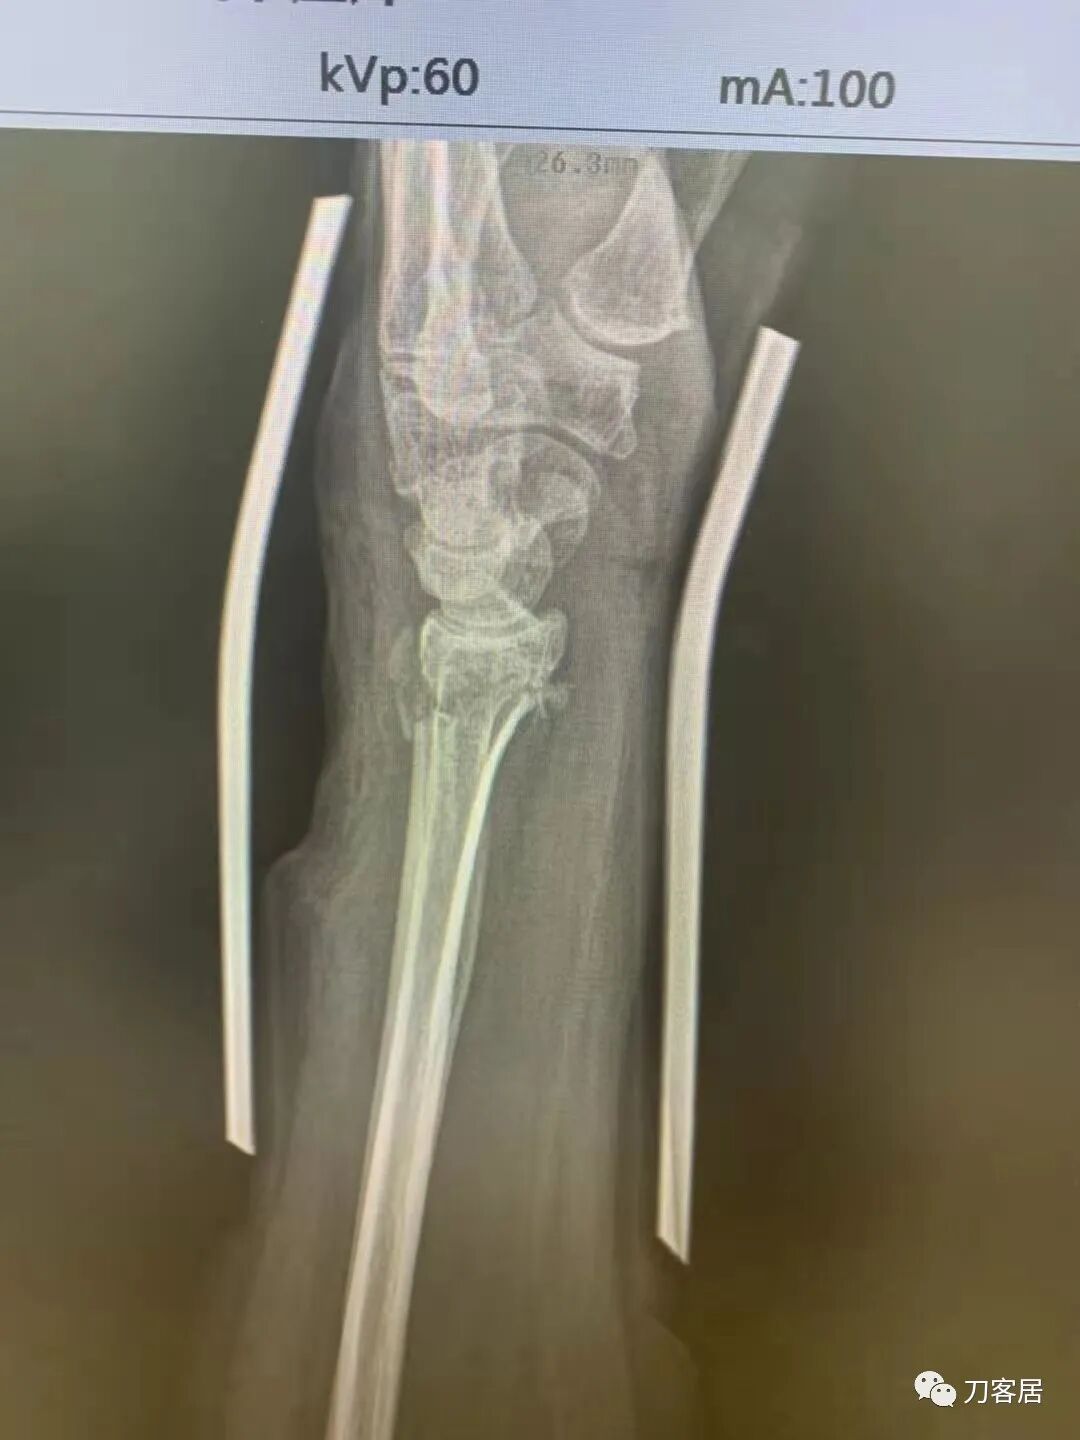

下面是这个6岁孩子,尺桡骨远端双骨折的术前及术后片子和外观照片。

1.  这是一个很简单的6岁儿童无移位的尺桡骨远端骨折。没有皮肤损伤,没有移位,没有骨折碎块儿。

2.  这个骨折处理起来也很简单,单纯的打石膏托或者中医的小夹板,或者正规的包括腕关节和肘关节的管型石膏外固定4周即可治愈该骨折。实在不行,如果这个孩子比较听话,不太调皮的话,用一本书,一个三角巾悬吊固定4周,都可以治愈该骨折。但是给这个患者用外固定架做了手术,而且桡骨远端的几颗克氏针距离骨折线太近,其中一枚克氏针进入到骨折间隙内。从这个术中图片来看,术者的外固定手术技术也有待于进一步的提高。毕竟术者应该还很年轻。从X线片来看,前臂及手的尺侧有不透光影,应该还使用了外固定石膏绷带托,而且我猜测应该是高分子的石膏绷带托,这个是纯属猜测,不一定是对的,不过如何解释前臂尺侧的不透光影呢?如果真是用了石膏绷带外固定的话,那为啥要做手术呢?外固定架术后就不该再用石膏绷带托辅助了。

3.  对于肢体骨折,特别是前臂长骨骨折,双骨折虽然不稳,但更容易手法复位,往往单骨折手法复位比较困难。该病例患儿6岁,尺桡骨双骨折,没有移位,所以根本就不存在需要复位的,直接打石膏外固定即可。孩子年龄越小,塑形能力越强,愈合速度越快,即使是有轻度的畸形骨愈合,在未来的塑形过程中,自然而然的恢复正常的力线和功能。对于该病例,即使是不干预,再过1-2周,只要骨折断端不移位,也能正常愈合而不留任何畸形。